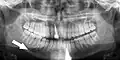

Панорамная рентгенограмма, показывающая дефект Стафне (отмечен стрелкой)